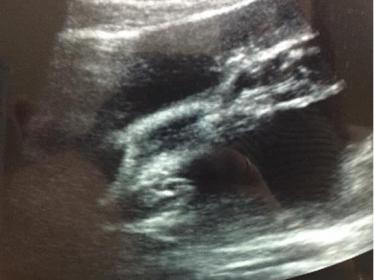

Hi can someone help me what they think the sex of baby is - I thought girl from the "three lines" one but the other one is throwing me because it looks protruding... they are both from the same scan but my area dont tell you sex of the baby so frustrating!!!

Attachment 38992Attachment 38993